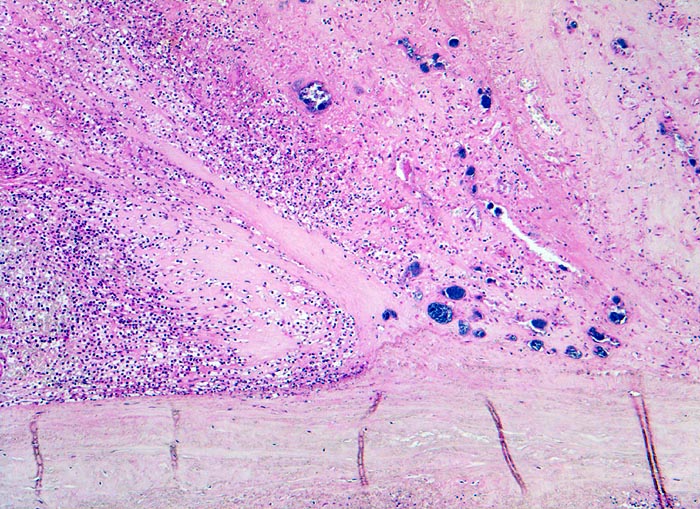

Histologisch findet sich bei ulzeropolypöser Endokarditis ein Fibrin-Thrombozytenthrombus, welcher von Bakterien durchsetzt ist (=Vegetation). Die Vegetation sitzt auf einem Klappendefekt an dessen Basis Granulationsgewebe einzusprossen beginnt, welches den Thrombus organisiert. Klappendefekte, Gefässeinsprossungen, verdickte Sehnenfäden (> 2848) oder Kommissurenverwachsungen (> 8389) der Taschenklappen weisen morphologisch auf eine abgeheilte Endokarditis hin.

• Längsschnitt durch Aorta, Aortenklappe und linkes Ventrikelmyokard.

• Oben im Bild die Aorta mit kleinem Fibroatherom.

• Abszedierende Entzündung der aortalen Adventitia ausgehend von septikopyämischen Streuherden.

• Ulzerierte Aortenklappe(ulcerosa).

• Dem ulzerierten Klappengerüst aufgelagerte polypöse Vegetation aus Fibrin und Granulozyten durchsetzt von blauen Kokkenbakterienkolonien (polyposa).

• Ausgedehnte frische Koagulationsnekrose (unsichtbare Zellkerne, Infiltrate neutrophiler Granulozyten) des linken Ventrikelmyokards unterhalb der Klappe.

• Mehrere septikopyämische Streuherde (blaue Bakterienhaufen in intramyokardialen Blutgefässen umgeben von Mikroabszessen).